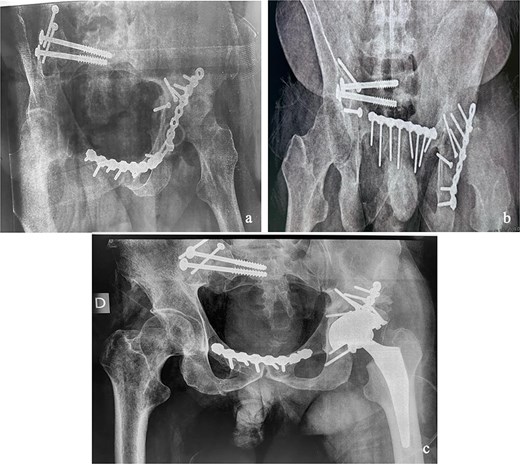

At the 10-month follow-up, the patient showed signs of left hip osteoarthritis with functional deterioration, for which a total ceramic-on-ceramic hip arthroplasty was performed, using a screw-fixed structural graft at the acetabulum (Fig. 3). At the final follow-up, 36 months postoperatively, the patient was walking unaided with the use of an anti-equinus splint on the left foot. The HHS was 85 and Majeed score was 86 [6, 7]. X-rays showed complete bone healing of all fractures and the acetabular graft. It should be noted that, during follow-up, the patient had a right femoral fracture that was successfully treated with a gamma nail (Fig. 4). Written informed consent were obtained from the patient.